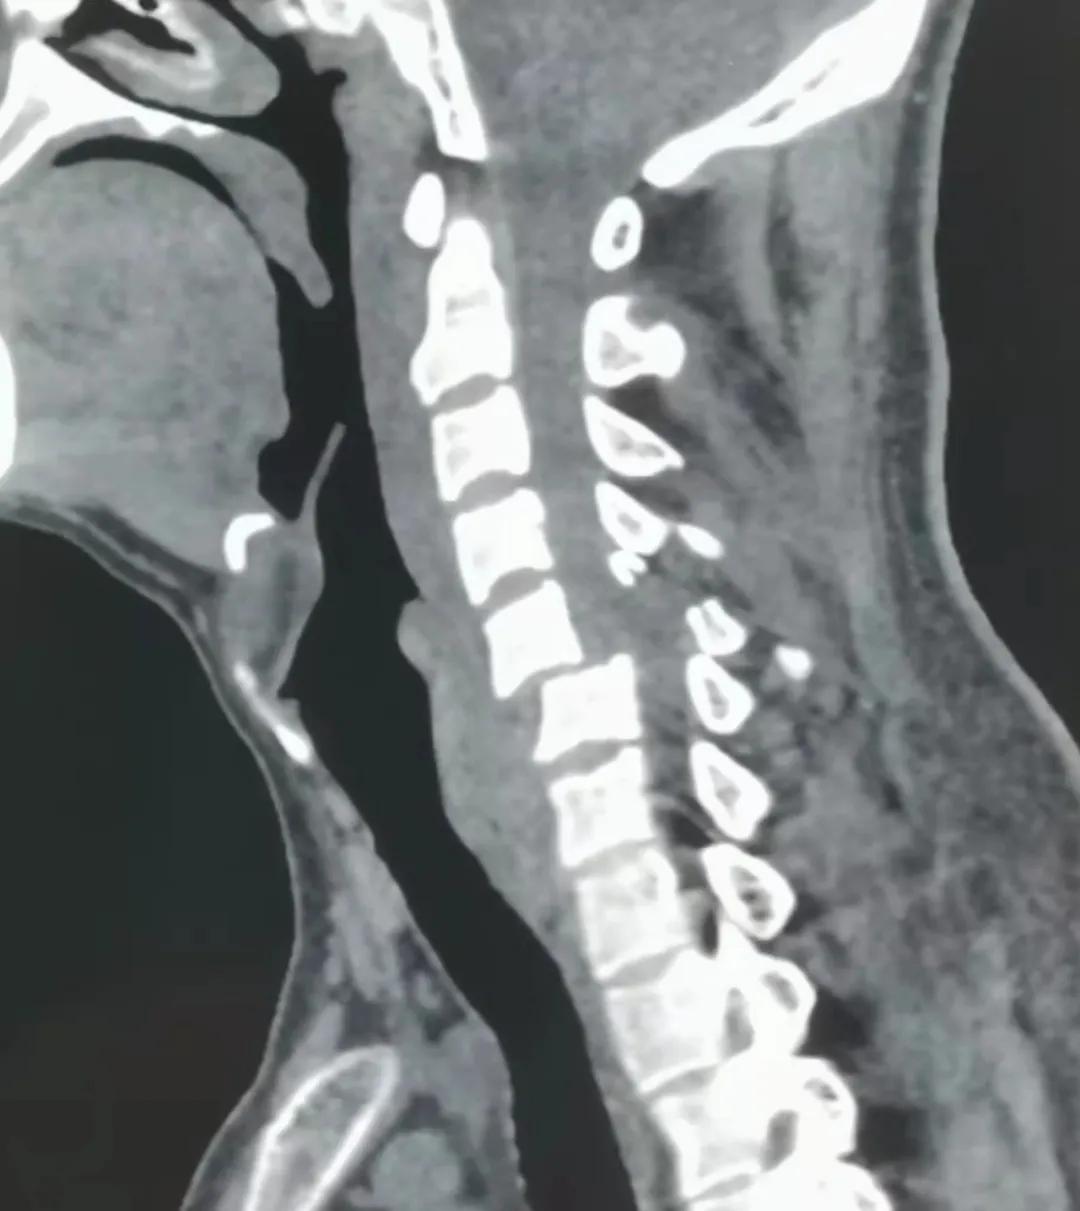

11月3日,某患者因头颈胸部外伤入院。经全面检查,诊断患者为“颈5骨折脱位,双侧关节突交锁、脊髓损伤”。患者入院后,康立星主任带领的骨一科专业团队高度重视,术前经过多次认真讨论,制定了科学周密的治疗方案。在手术麻醉科刘占波主任和马东风医生的通力配合下,康立星主任带领骨科医疗团队为患者施行“一期颈椎前后路联合骨折复位内固定术”。手术过程顺利,未输血,术中颈椎脱位完全复位,固定钢板螺钉位置良好,目前患者恢复良好。